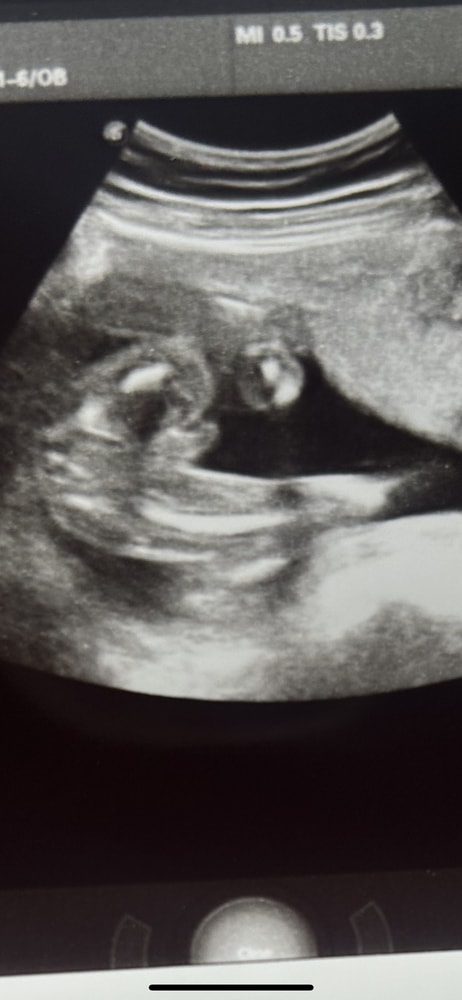

Могут ли перепутать половой орган с пуповиной ?

На узи 21 неделя беременности долго не могли увидеть пол малыша

Через какое то время показалось что мальчик . Подскажите может ди быть ошибочным ?